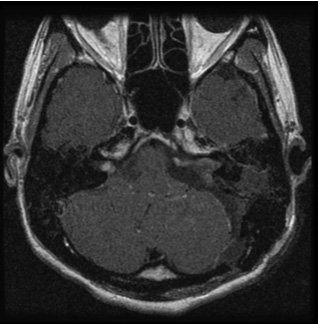

また高齢者でも手術は有益です。図2の症例は80歳の男性症例ですが、10年来右耳難聴で聴神経腫瘍の診断はつけられておりましたが、治療希望せず放置されておりました。しかし歩行障害が進行し当院に紹介されてまいりました。

造影MRIでは大型の腫瘍を認め、周囲の脳幹や小脳が強く圧迫され腫れています。手術にて90%の腫瘍摘出を行い、脳の圧迫もとれ、症状も改善し、治療後3年たった現在でも元気で外来に通っていらっしゃいます。

図2:80歳男性 歩行障害をきたした大型神経鞘種

(左図)治療前MRI:顕著な脳の圧迫と脳浮腫を認める

(左図)術後2年後のMRI:薄い残存腫瘍をみとめるが再増大なく、脳の圧迫は改善している